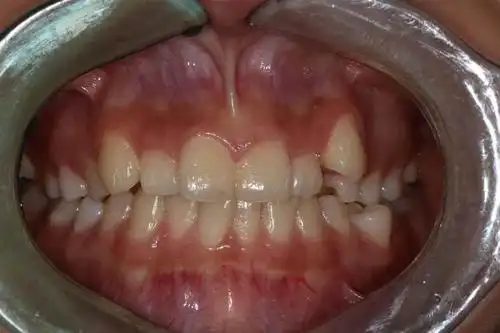

厦门牙齿矫正虎牙不好看为什么不能拔掉

为什么拔牙矫正中,医生一般都不建议拔虎牙?

可爱的虎牙有可能成为可怕的口腔隐患

虎牙烦恼知多少?